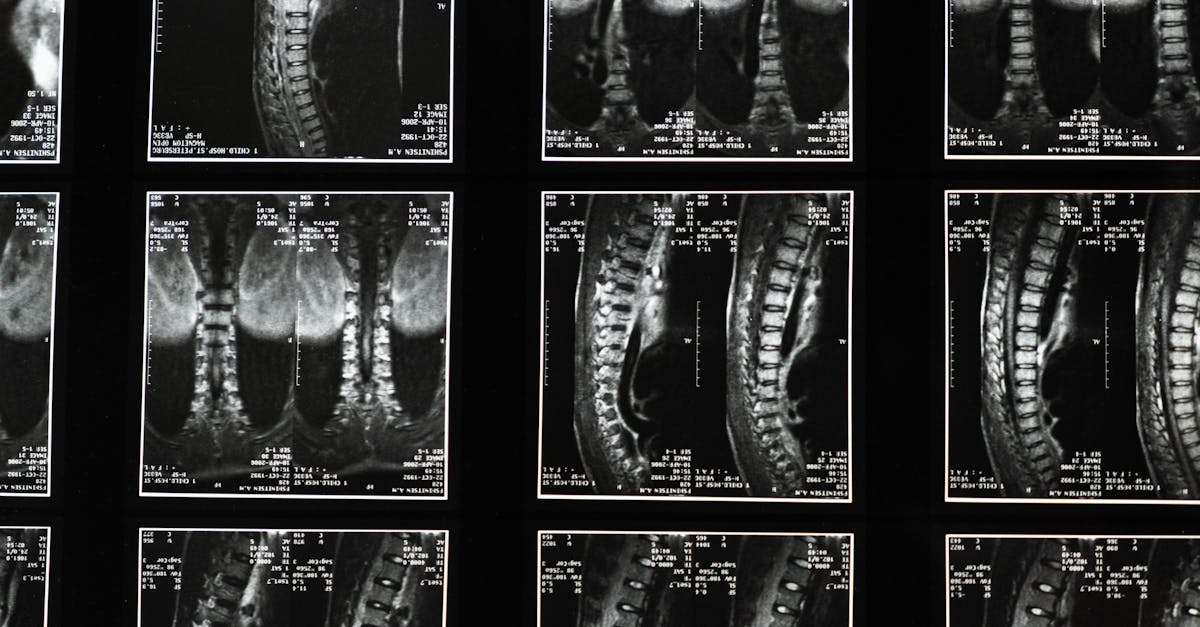

EN BREF La décompression neurovertébrale est une méthode innovante conçue pour prévenir les hernies discales futures en soulageant la pression sur les disques intervertébraux. À Montréal, […]

EN BREF La décompression neurovertébrale est une méthode thérapeutique novatrice visant à prévenir les récidives de pathologies spinales, notamment celles liées aux hernies discales. Accessible à […]

En bref, la décompression neurovertébrale est une méthode thérapeutique non chirurgicale qui vise à améliorer la régénération des tissus en réduisant la pression sur les disques […]

EN BREF La décompression neurovertébrale est une méthode thérapeutique non invasive conçue pour prévenir la progression des pathologies spinales telles que les hernies discales et la […]